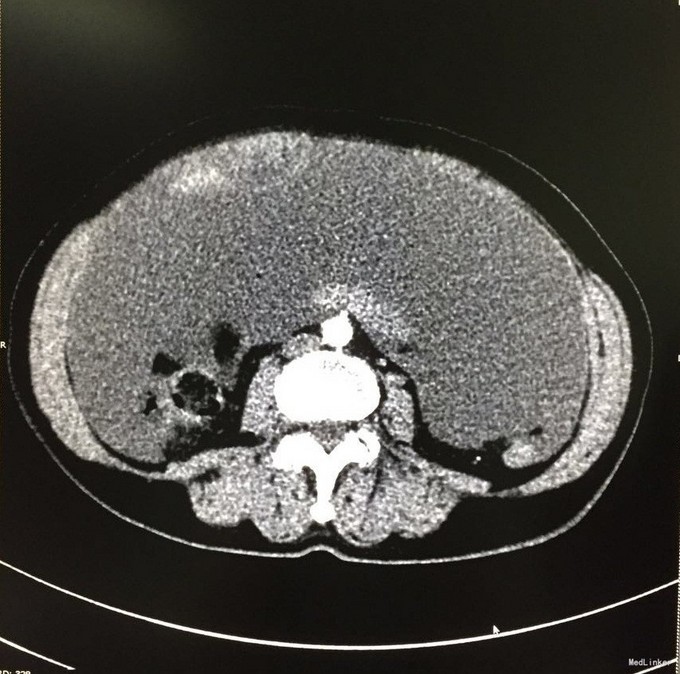

查体:腹膨隆,可及一包块,质中,活动可,边缘不清,位置较固定,无红肿热痛,无压痛。 辅查:我院CT:盆腔巨大囊性肿块,大小约15x10cm,考虑附件来源恶性肿瘤,囊腺癌可能;肝内一结节状稍低密度影,增强后轻度强化,转移瘤可能;胆囊多发结石;盆腹腔积液。肿瘤标志物:CEA:33.2U/mL。

入院诊断:腹腔肿物、胆囊结石、腹水。入院后行剖腹探查术,术中见腹腔大量胶冻样物约5000ml,左卵巢见一20x20cm囊性包块,包膜不完整,可见破溃口,内含胶冻样物,右附件及子宫未见明显异常。阑尾见3x3cm大小的粘液样肿块,腹膜、大网膜、肠管表面均有胶冻样物覆盖。遂行腹式双附件切除术+回盲部肿物切除术+腹膜活检术。术中冰冻病理示:左卵巢粘液囊腺瘤,局部增生活跃。术后病理示:左卵巢粘液性囊腺瘤,阑尾低级别粘液性腺瘤。术后诊断:左卵巢粘液性囊腺瘤并自发破裂,阑尾低级别粘液性腺瘤,胆囊结石。